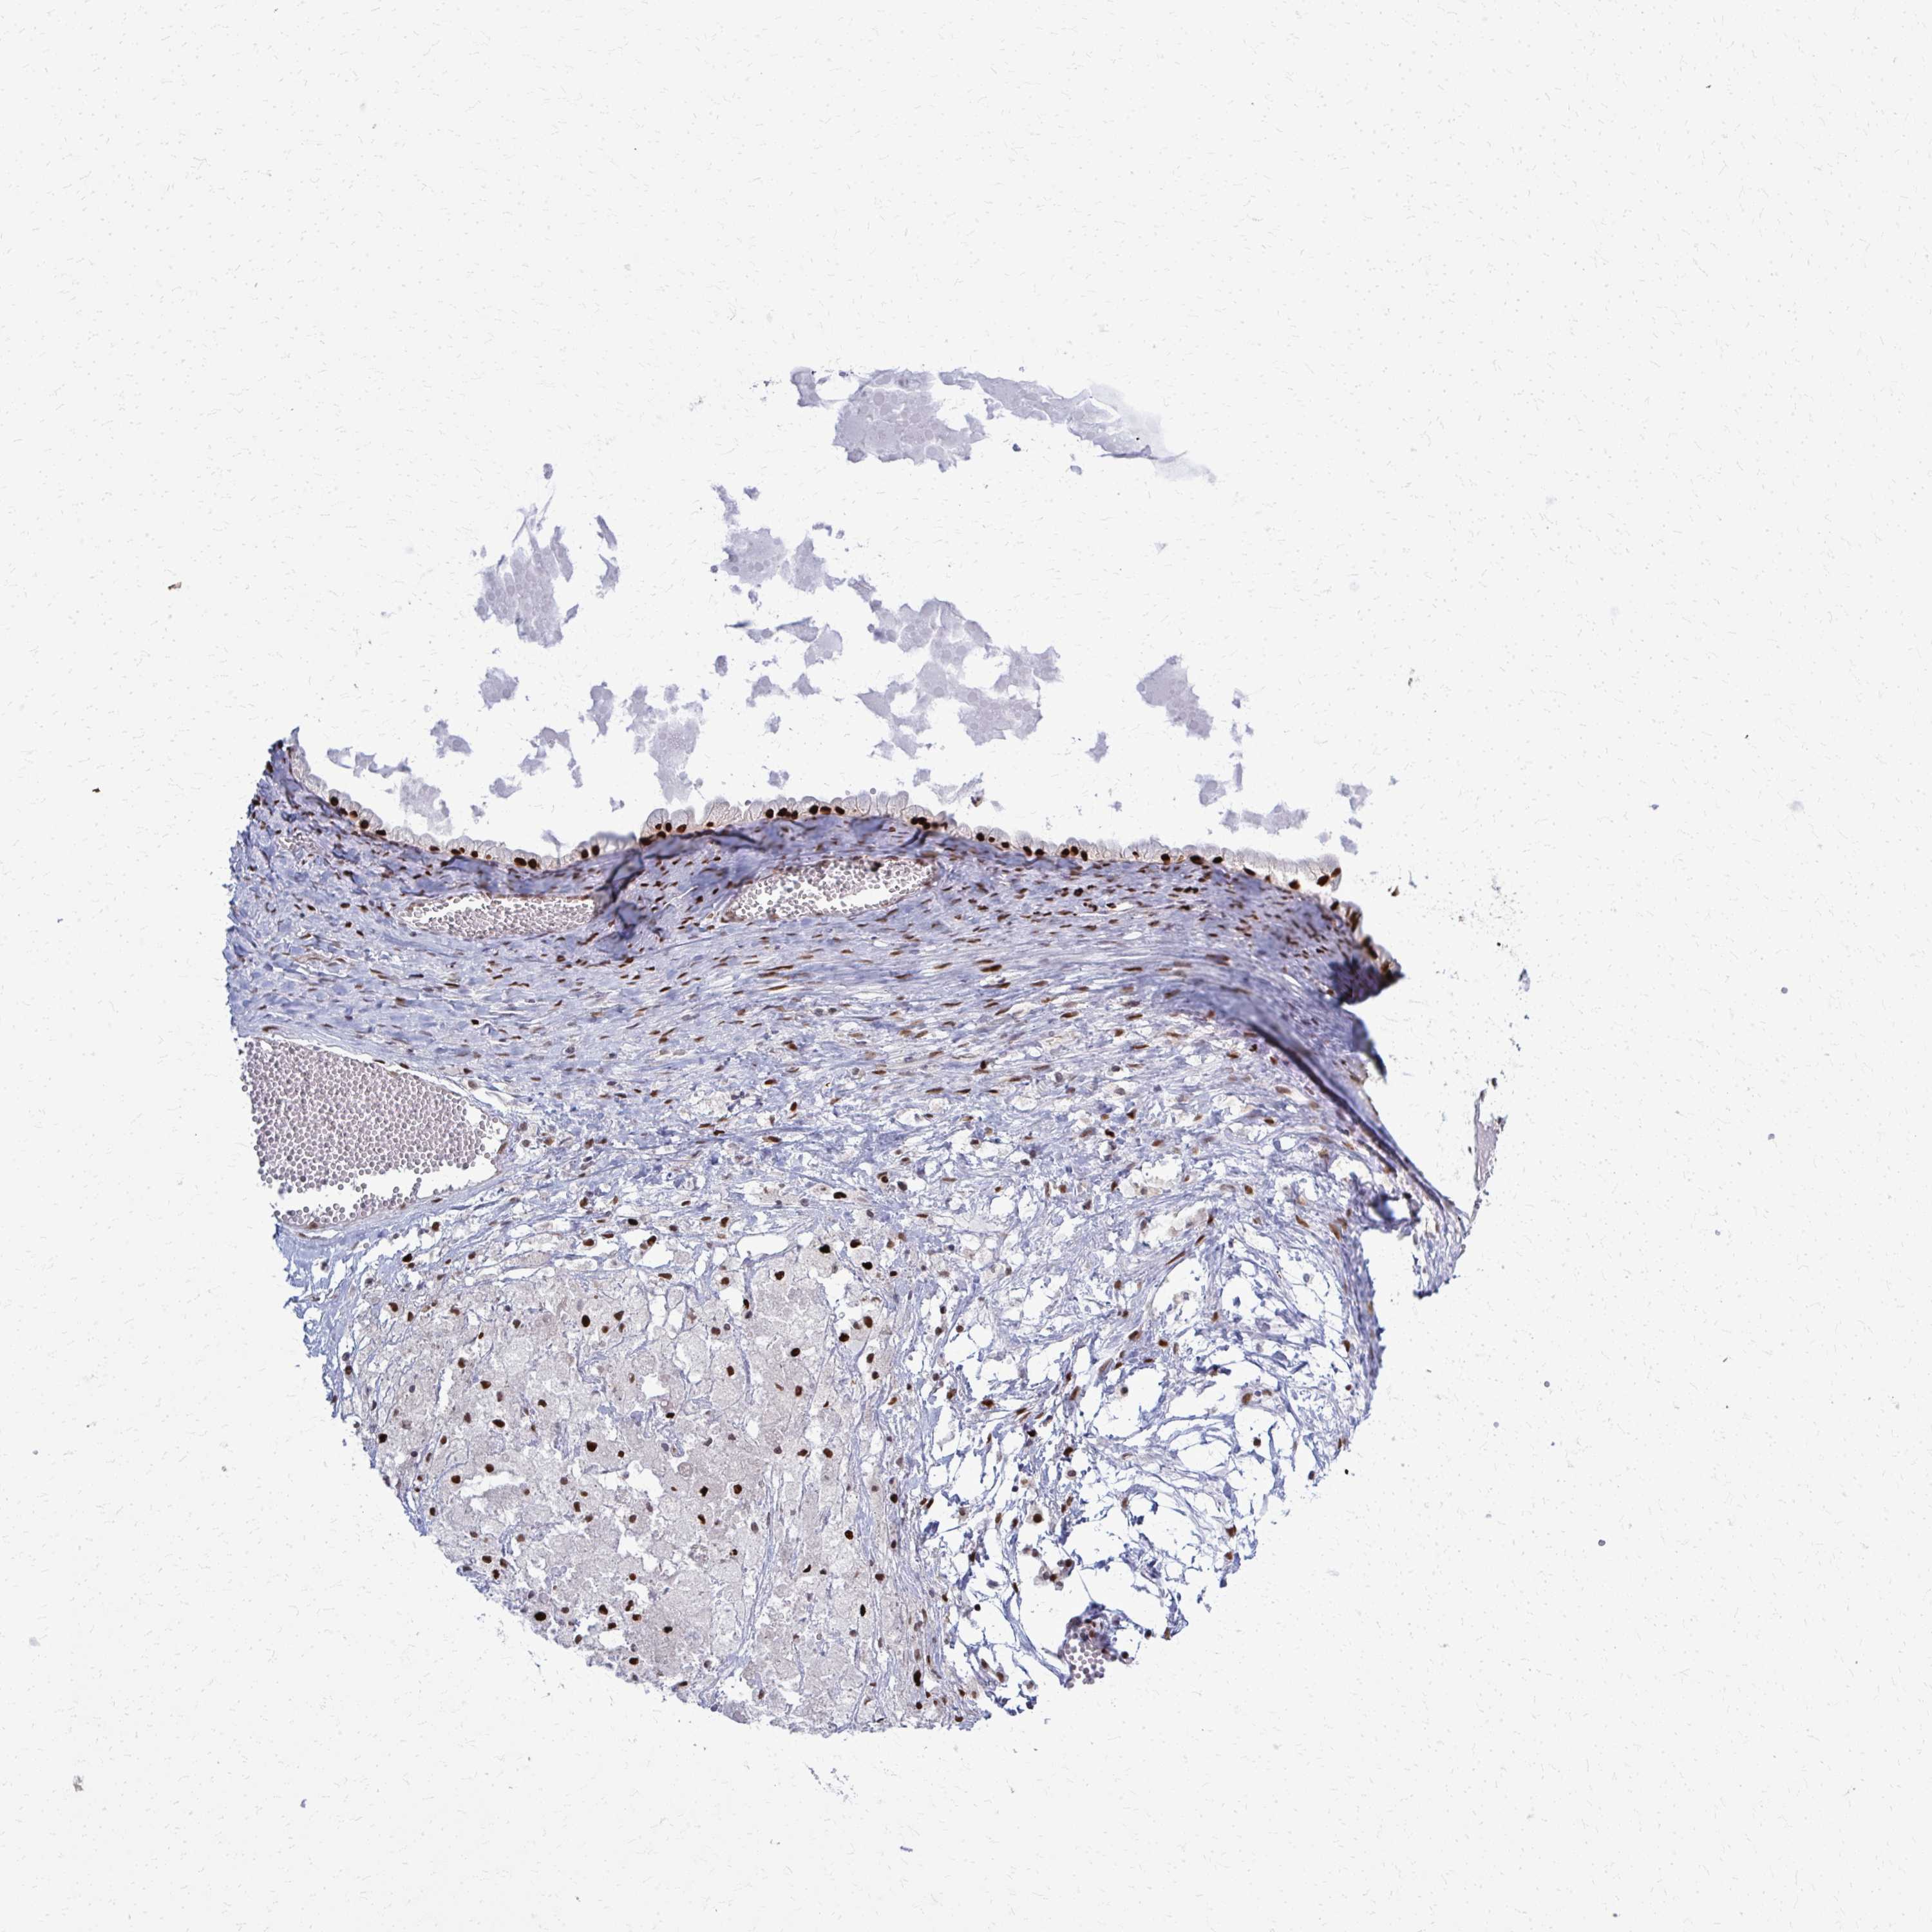

OVARIAN CANCER - Protein expressioni

A mouse-over function shows sample information and annotation data. Click on an image to view it in a full screen mode. Samples can be filtered based on level of antibody staining by selecting one or several of the following categories: high, medium, low and not detected. The assay and annotation is described here.

Note that samples used for immunohistochemistry by the Human Protein Atlas do not correspond to samples in the TCGA dataset.

Antibody stainingi

Antibody staining in the annotated cell types in the current human tissue is reported as not detected, low, medium, or high, based on conventional immunohistochemistry profiling in selected tissues. This score is based on the combination of the staining intensity and fraction of stained cells.

Each image is clickable and will lead to virtual microscopy that enables deeper exploration of all samples and also displays staining intensity scores, fraction scores and subcellular localization as well as patient and tissue information for each sample.

Antibody HPA059632

Staining

High

Medium

Low

Not detected

Intensity

Strong

Moderate

Weak

Negative

Quantity

>75%

75%-25%

<25%

None

Location

Nuclear

Cytoplasmic/membranous

Cytoplasmic/membranous,nuclear

Cystadenocarcinoma, serous, NOS

Carcinoma, NOS

Cystadenocarcinoma, mucinous, NOS

Carcinoma, endometroid